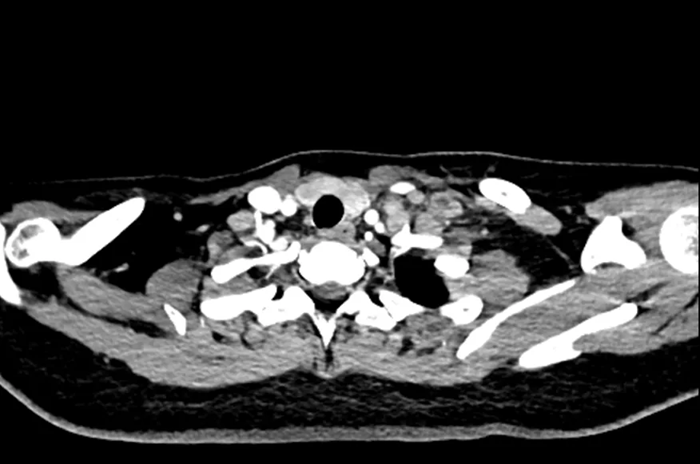

Hình ảnh chụp CT của nữ sinh 20 tuổi

Gần đây, một phụ nữ ngoài 20 tuổi đến khám tại Bệnh viện Nhân dân Đông Hoản (Quảng Đông, Trung Quốc) vì phát hiện khối u ở cổ trái trong khoảng một tuần.

Trước đó, cô cảm thấy vùng cổ đau nhẹ và sờ thấy một khối cứng kích thước gần bằng quả trứng gà. Khối u ấn vào có cảm giác đau nhưng không đỏ, không sưng. Điều đáng nói là cô không hề có triệu chứng tiêu hóa rõ ràng như đau bụng, đầy hơi hay sốt, ăn uống và đại tiện vẫn bình thường.

Sau khi nhập viện để kiểm tra toàn diện, bác sĩ tiến hành nội soi dạ dày và sinh thiết hạch cổ. Kết quả giải phẫu bệnh cho thấy bệnh nhân mắc ung thư biểu mô tuyến kém biệt hóa, trong đó có thành phần ung thư tế bào nhẫn - một dạng ung thư dạ dày ác tính cao.

Chụp CT cho thấy khối u đã di căn toàn thân, không còn chỉ định phẫu thuật. Các bác sĩ chỉ có thể đề nghị điều trị bằng hóa trị, xạ trị hoặc liệu pháp miễn dịch nhằm kiểm soát bệnh.